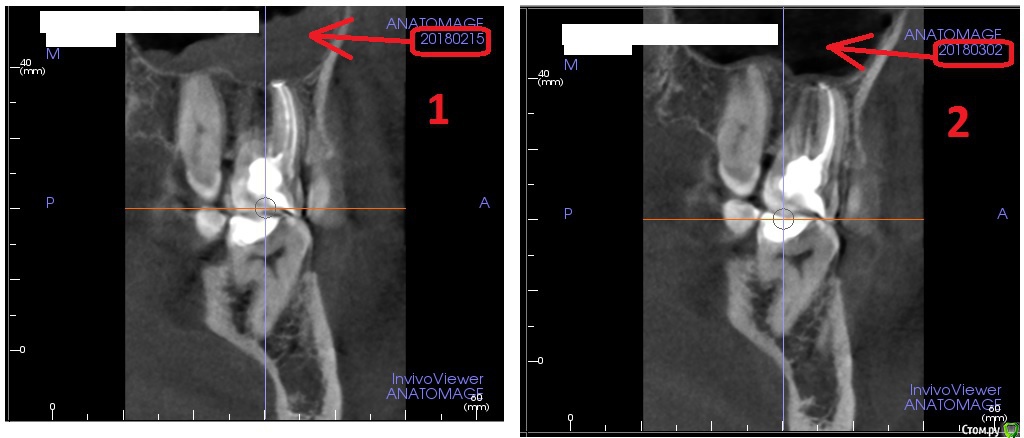

usilitel Опубликовано 21 ноября, 2018 Автор Поделиться Опубликовано 21 ноября, 2018 (изменено) Само в организме ничего не проходит, тем более воспаление в пазухе!Тогда как объяснить это:?Разница между 1-ым и 2-ым снимками = 2 недели, на 2-ом воспаление прошло. Никакого лечения в этот период не было, даже таблетки не пил. 1-ый снимок сделан через 3 дня после депульпации зуба.Может слизистая "умерла"? Типа некроз слизистой гайморовой пазухи. Такое бывает вообще? Изменено 21 ноября, 2018 пользователем usilitel Ссылка на комментарий